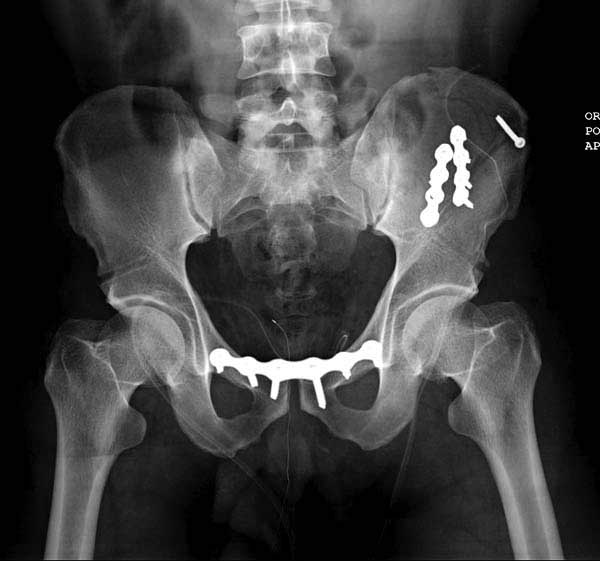

Здесь представлен случай 38 летнего больного (падение с высоты 9 метров) с нарушением тазового кольца. При поступлении для стабилизации передне-нижний аппарат наружной фиксации и на 6й день, вчера, операция из двух доступов.

Представлены снимки техники проведения стержней. Через место прикрепления прямой мышцы в Inferior Iliac Spine в направления вырезки создается жесткость. Weber clamp изнутри таза для репозиции, и фиксация после репозиции перелома крыла подвздошной кости. Наружный аппарат удален, нагрузка предполагается через два месяца.